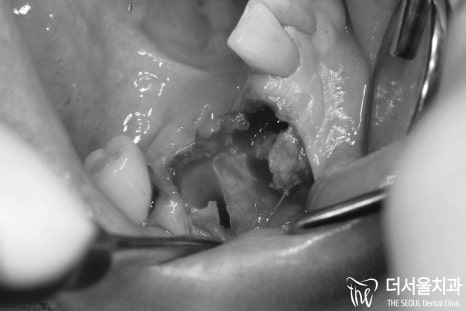

구강 내를 살펴보면 오래된 브릿지가

어금니 부근으로 자리를 잡고 있었는데요.

정밀검사를 하기 전에도 알 수 있었습니다.

바로 ‘이차우식’이 생겨 통증이 생겼다는걸요..

문제는.. 이게 다가 아니었습니다.

바로 # 43 하방의 과잉치였는데요.

사실 예전에 치료받았던 곳에서

이 과잉치 때문에 인공치아를 심을 수 없다면서

브릿지로 진행을 하셨다네요.